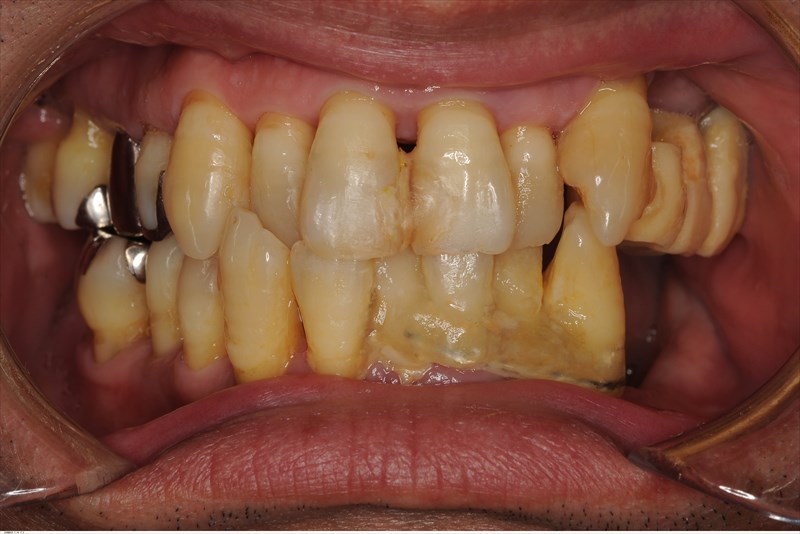

前の先生の苦労が分かります、歯の揺れが止められないのですべてボンドでくっつけてありました。前のF先生ありがとうございます。左下は歯がすでになく他の歯はすべてグラグラ。。

歯科ドックを行うと歯のポジション(力の逃げ道がない咬みあわせ)の問題が大きい事が分かりました。我々が扱う中等度~重度の歯周病の患者さまはこのように歯のポジションが悪く二次性咬合性外傷という状態になっている事が多くそのせいで負のスパイラルになり炎症が起き力の影響で歯が揺れ動きまた炎症が起き力がコントロールできない状態に。